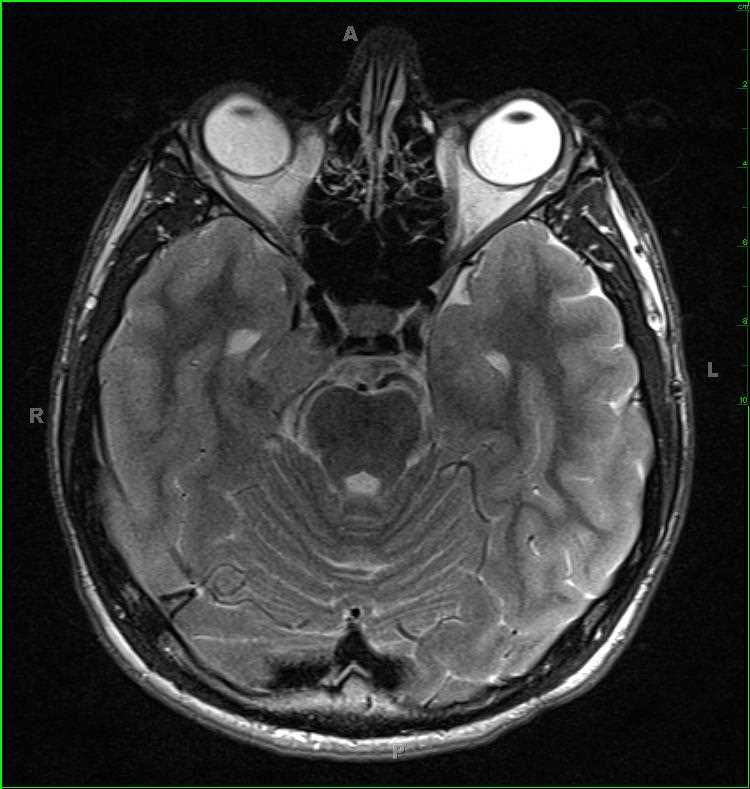

Sinonasal Undifferentiated Carcinoma (SNUC)

63-year-old female with a longstanding history of anosmia and nasal obstruction. There is a T1-hypointense, T2/FLAIR-isointense, enhancing nasal cavity mass. The lesion restricts diffusion. The mass extends into the anterior cranial fossa, including involvement of the olfactory fossa. A differential of esthesioneuroblastoma, squamous cell carcinoma, and sinonasal undifferentiated carcinoma was given. There are T1-hyperintensities in the bilateral maxillary antra and ethmoid air cells compatible with retained secretions and debris secondary to obstruction of the sinus outflow tracts. On biopsy, this mass was a sinonasal undifferentiated carcinoma or SNUC. SNUC is a rare and highly aggressive neoplasm of the paranasal sinuses. Tumors tend to be large and advanced at initial presentation. Prognosis is poor, with treatment typically entailing wide excision followed by radiation and chemotherapy.